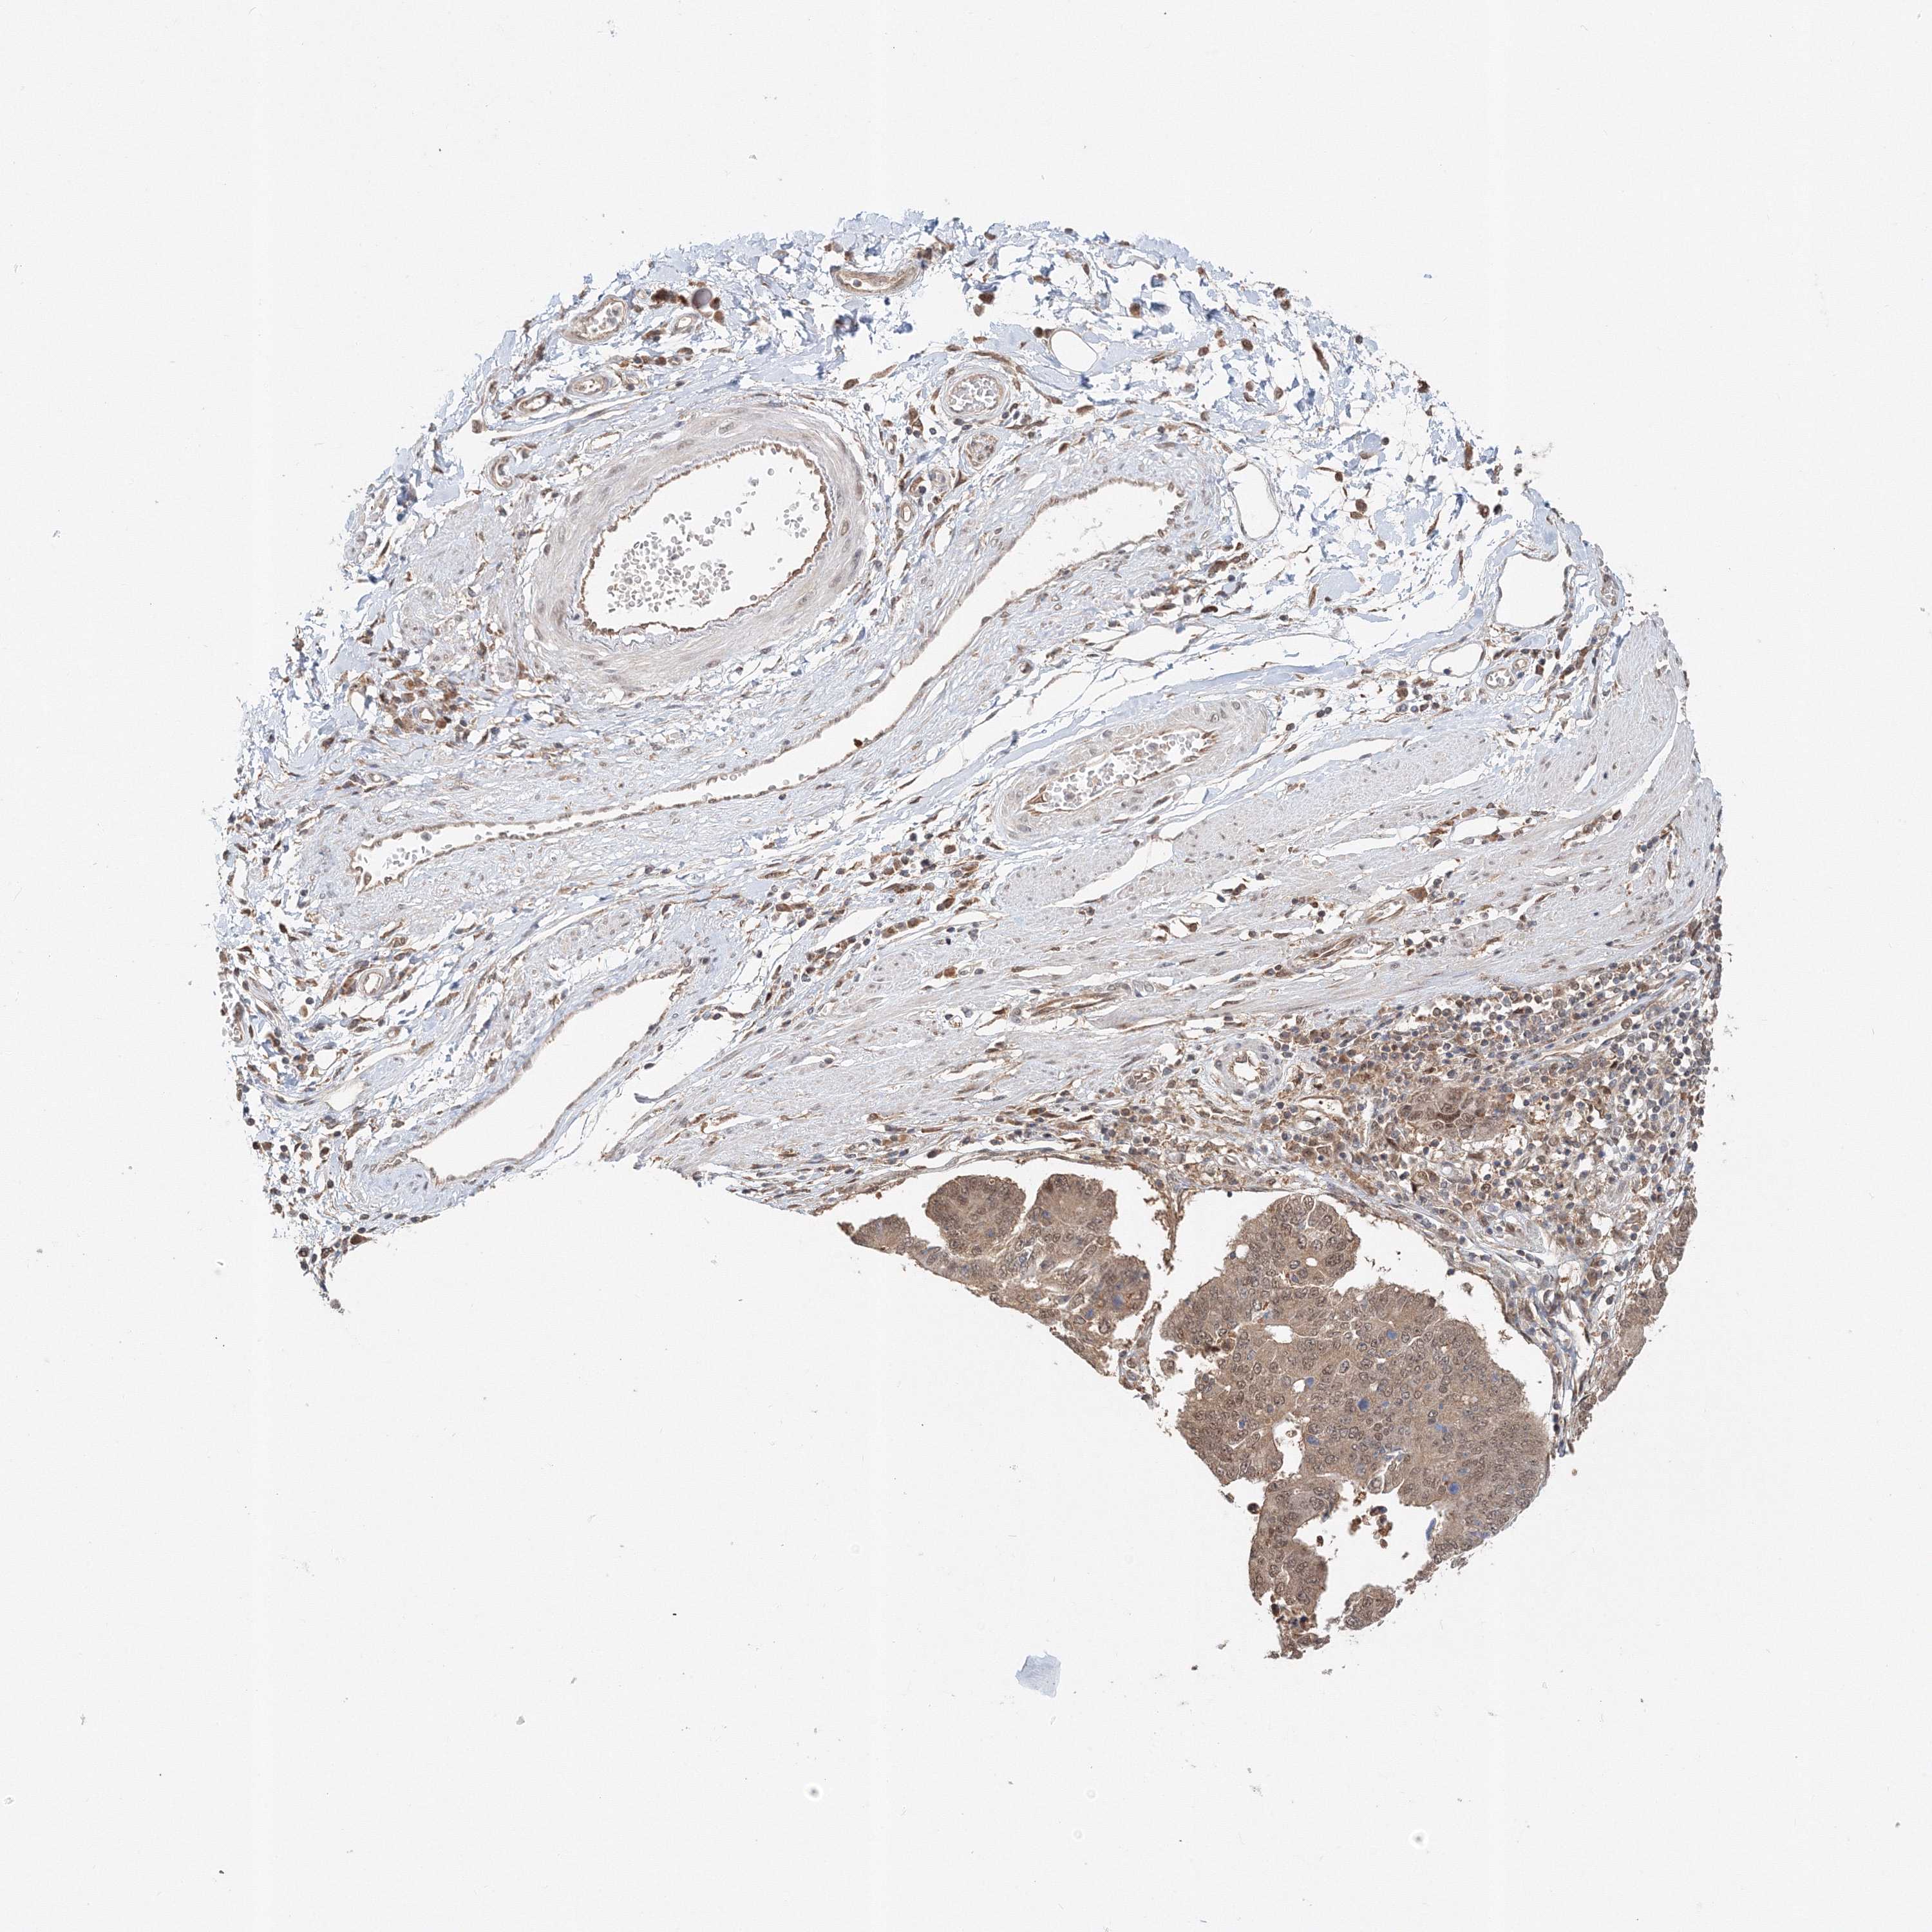

STOMACH CANCER - Protein expressioni

A mouse-over function shows sample information and annotation data. Click on an image to view it in a full screen mode. Samples can be filtered based on level of antibody staining by selecting one or several of the following categories: high, medium, low and not detected. The assay and annotation is described here.

Note that samples used for immunohistochemistry by the Human Protein Atlas do not correspond to samples in the TCGA dataset.

Antibody stainingi

Antibody staining in the annotated cell types in the current human tissue is reported as not detected, low, medium, or high, based on conventional immunohistochemistry profiling in selected tissues. This score is based on the combination of the staining intensity and fraction of stained cells.

Each image is clickable and will lead to virtual microscopy that enables deeper exploration of all samples and also displays staining intensity scores, fraction scores and subcellular localization as well as patient and tissue information for each sample.

Antibody HPA036921

Antibody HPA036922

Staining

High

Medium

Low

Not detected

Intensity

Strong

Moderate

Weak

Negative

Quantity

>75%

75%-25%

<25%

None

Location

Nuclear

Cytoplasmic/membranous

Cytoplasmic/membranous,nuclear

Adenocarcinoma, NOS